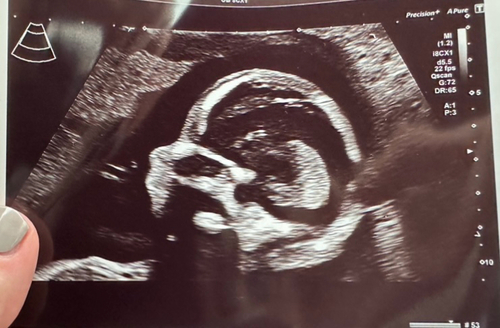

Das ist mein Ultraschallbild aus der 21SSW beim Organscreening. Er wiegt ca 400 gramm und ist 24 cm groß.